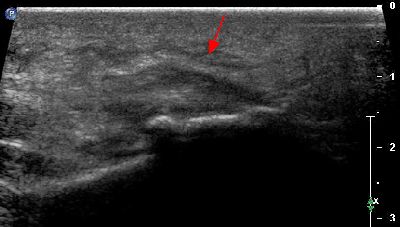

Tendinopatia del muscolo peroneo lungo tendine del m. peroneo lungo

Tendinopatia del muscolo peroneo lungo (2) tendine del m. peroneo lungo